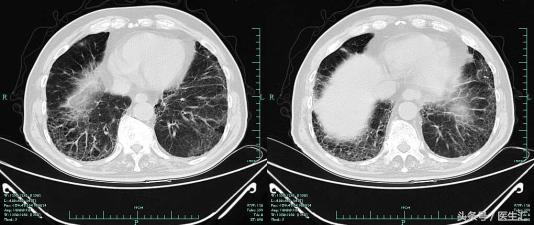

2013-9-25肺CT

2013-10-13 肺部CT:慢支、肺气肿。两肺间质性病变,对照13.9.25老片右肺斑片影增多,感染考虑。右上肺钙化灶。